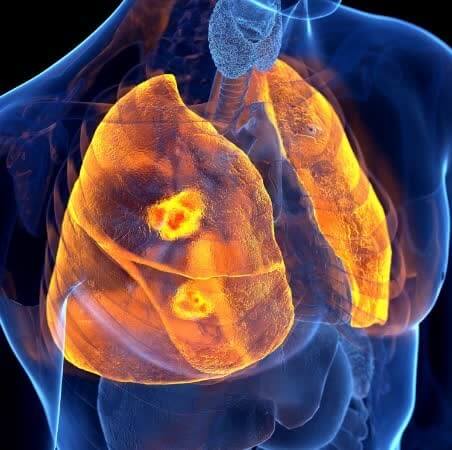

6) 호흡곤란

폐에 발생하는 성인 폐렴 증상인 만큼 해당 문제로 인해 호흡곤란을 느낄 수 있습니다. 예전에 비해서 호흡 자체에 불편함을 느끼고 통증이 느껴지는 경우도 있습니다.

폐렴 원인